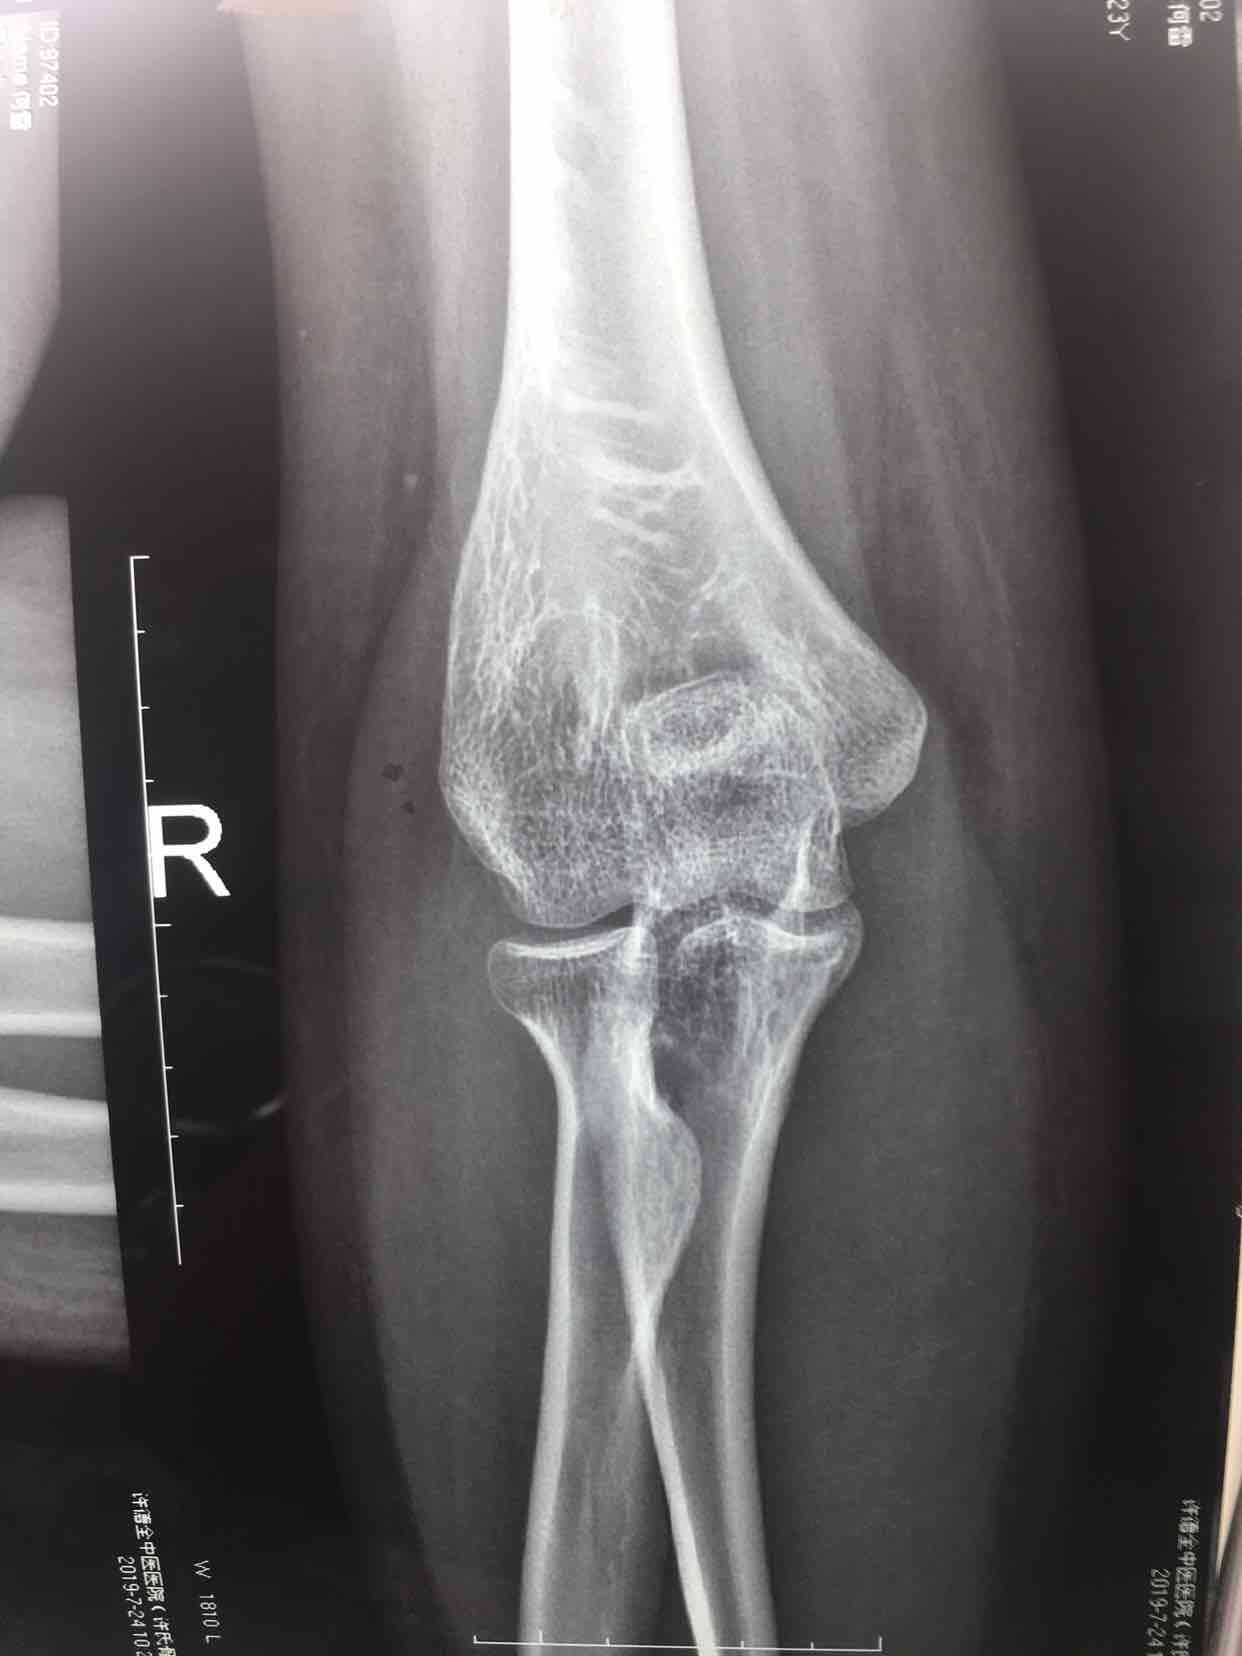

尺骨鹰嘴骨折(切复内固定术)

骨折 鹰嘴骨折

摔伤后右肘部肿痛,活动受限1小时入院。既往身体健康,无特殊不良嗜好。

生命体征平稳,心肺复未见异常。右肘部肿胀明显,局部皮色皮温正常,压痛明显,可及骨檫音,末梢血运感觉正常。

诊断右尺骨鹰嘴骨折在臂丛麻醉下行切复内固定术,术后抗炎,消肿等处理。